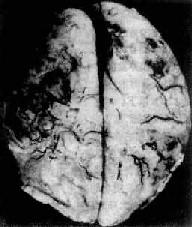

图16-11 化脓性脑膜炎 蛛网膜下腔充满脓性渗出物,血管扩张充血 【临床病理联系】 急性化脓性脑膜炎在临床上除了发热等感染性全身性症状外,常有一系列神经系统症状,表现为: (1)颅内压升高症状:头痛,喷射性呕吐,小儿前囟饱满等。这是由于脑血管充血,蛛网膜下腔渗出物堆积,蛛网膜颗粒因脓性渗出物阻塞而影响脑脊液吸收所致,如伴有脑水肿,则颅内压升高更加显著。 (2)脑膜刺激症状:颈项强直。炎症累及脊髓神经根周围的蛛网膜、软脑膜及软脊膜,致使神经根在通过椎间孔处受压,当颈部或背部肌肉运动时可引起疼痛,颈项强直是颈部肌肉对上述情况所发生的一种保护性痉挛状态。在婴幼儿,由于腰背肌肉发生保护性痉挛可引起角弓反张(episthotonus)的体征。此外,Kerning征(屈髋伸膝征)阳性,是由于腰骶节段神经后根受到炎症波及而受压所致,当屈髋伸膝试验时,坐骨神经受到牵引,腰神经根因压痛而呈现阳性体征。 (3)颅神经麻痹:由于基底部脑膜炎累及自该处出颅的Ⅲ,Ⅳ,Ⅴ,Ⅵ,Ⅶ对颅神经,因而引起相应的神经麻痹征。 (4)脑脊液的变化:压力上升,混浊不清,含大量脓细胞,蛋白增多,糖减少,经涂片和培养检查可找到病原体。脑脊液检查是本病诊断的一个重要依据。 结局和并发症 由于及时治疗和抗菌素的应用,大多数患者可痊愈,病死率已由过去70%~90%降低到50%以下。如治疗不当,病变可由急性转为慢性,并可发生以下后遗症:①脑积水:由于脑膜粘连,脑脊液循环障碍所致;②颅神经受损麻痹:如耳聋,视力障碍,斜视、面神经瘫痪等;③脑底脉管炎致管腔阻塞,引起相应部位脑缺血和梗死。 暴发性脑膜炎球菌败血症是暴发型流行性脑脊膜炎的一种类型,多见于儿童。本病起病争骤,主要表现为周围循环衰竭、休克和皮肤大片紫瘢。与此同时,两侧肾上腺严重出血,肾上腺皮质功能衰竭,称为沃-弗(Waterhouse-Friederichsen)综合片,其发生机制主要是大量内毒素释放所引起的弥漫性血管内凝血,患者脑膜变化轻微,病情凶险,一般在起病24小时内死亡。 2.结核性脑膜炎 详见第十八章 (二)脑脓肿 【病因】 脑脓肿的致病菌既往以葡萄球菌,链球菌,肺炎球菌等需氧菌为多见,近年来厌氧菌属之链球菌,无芽胞革兰阴性菌,类杆菌等亦成为常见的致病菌。 感染途径 1.直接蔓延病菌通过颅骨骨折伤口或局部感染灶直接蔓延至脑而引起的脑脓肿,其中常见的局部感染灶为中耳炎、乳突炎和鼻窦炎。头皮炎症有时也可成为感染源。抗菌素广泛应用以来,上述病灶的发病率已显著下降,脑脓肿来源于直接蔓延感染者也明显减少。 2.血源性感染病菌来自体内感染灶(肺脓肿、细菌性心内膜炎等)经血流至脑而引起脑脓肿。特别值得注意的是在紫绀性先天性心脏病患者中,脑脓肿的发生率较高,这一情况可能与左右心之间短路的存在以及肺过滤细菌的作用不良有关。 【病理变化】 脑脓肿的部位与数目因感染途径不同而异。一般由局部炎症灶直接蔓延所致的脑脓肿常为单个,其中耳源性(中耳炎、乳突炎)脑脓肿多见于颞叶或小脑;鼻窦(额窦)炎引起的脑脓肿多见于额叶。血源性感染所致者常为多发性,可分布于大脑各部。 脑脓肿的发展规律和形态与全身其它器官的脓肿相似。急性脓肿发展迅速,境界不清,无包膜形成,可向四周扩大,甚至破入蛛网膜下腔或脑室,引起脑室积脓,可迅速致死。慢性脓肿边缘毛细血管和纤维母细胞(源于血管壁)增生明显,并伴有淋巴细胞和巨噬细胞浸润,形成炎性肉芽组织和纤维包膜,境界清楚。脓肿周围脑组织水肿明显,并伴有星形胶质细胞增生(图16-12)。

图16-12 慢性脑脓肿 右侧颞叶的脑脓肿与侧脑室相通 【临床病理联系】 脑脓肿的临床表现主要有两个方面: 1.颅内压升高由于脓肿占位性效应及其周围明显的脑水肿所致,临床表现为头痛、呕吐、昏迷、抽搐,小儿前囟饱满。 2.局灶性症状局部脑组织破坏可引起相应的功能障碍,临床表现按病变部位而异,如大脑脓肿可引起半瘫、抽搐,小脑脓肿可引起共济失调等。 【结局】 脓肿小,治疗及时,病灶可被完全吸收而消散。脓肿大,发展迅速,可引起颅内压增高和脑疝形成,后果严重。如脓肿破裂引起脑室炎和脑膜炎,其后果严重,常可致死,如及时进行手术和抗菌治疗,可使死亡率减少到20%以下。